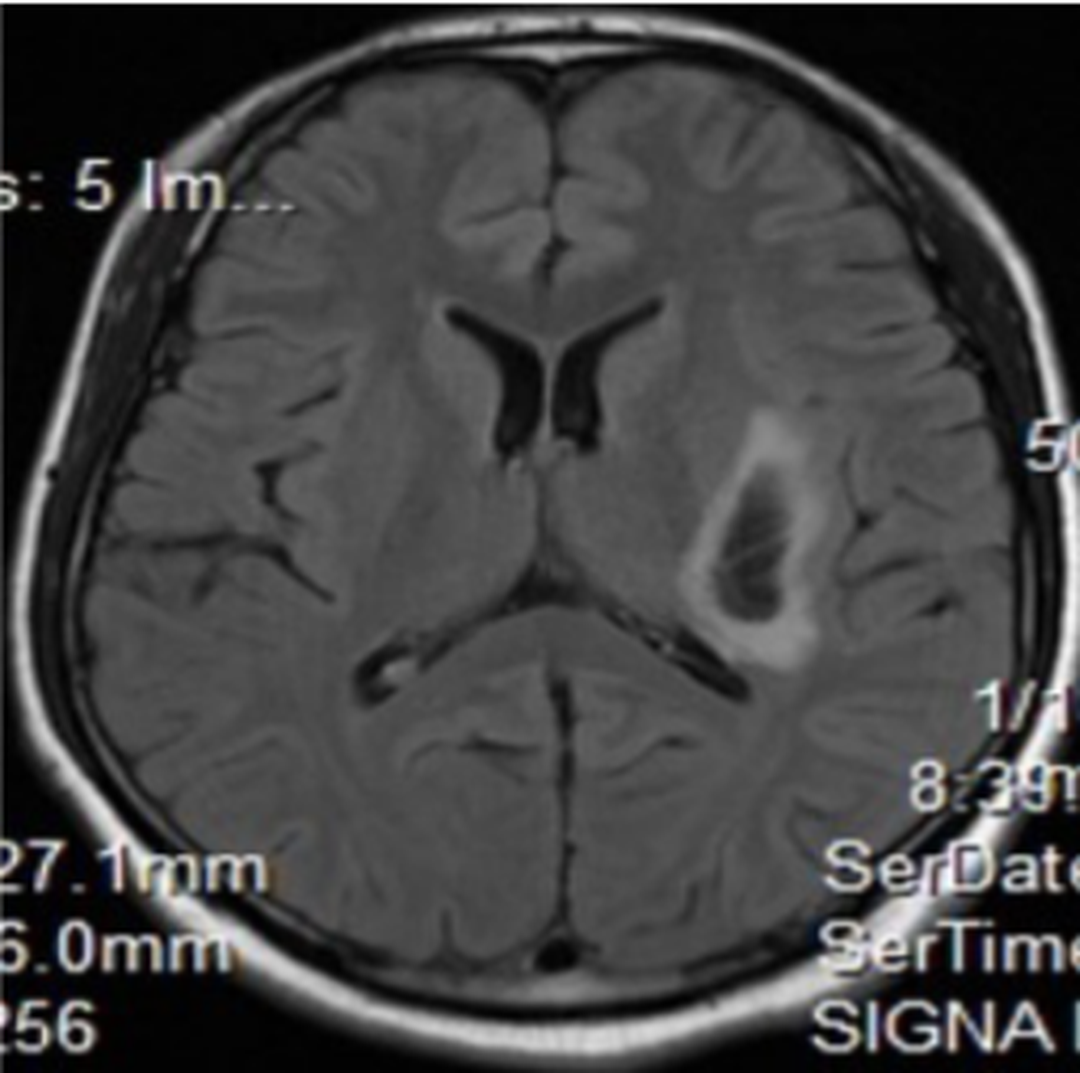

Pure sensory stroke is a rare entity since stroke is almost always accompanied by few motor symptoms. Most common cause of pure sensory stroke is lacunar hemorrhage or lacunar infarction. However, a report presented a case of putamen hemorrhage that manifested in pure sensory stroke. A 27-year-old patient, with no known comorbidities, presented to ER with complain of numbness on right side of the body for approximately 10 hours. He reported no visual as well as the motor symptoms. Examination revealed otherwise healthy male, with decreased sense of touch and pain on right side of the body. All other neurological tests were normal. Blood panel and metabolic profile were within normal parameters. MRI revealed hematoma on left putamen region. 20% mannitol was given 8 hourly via dosing at 0.5g/kg. Source Pure Sensory Stroke due to Putamen Bleed: A Case Report https://www.researchgate.net/profile/Ivaturi_Venkata_Nagesh/publication/344160713_Pure_sensory_stroke_due_to_putamen_bleed/links/5f57135c92851c250b9cfa04/Pure-sensory-stroke-due-to-putamen-bleed.pdf Image via https://www.researchgate.net/profile/Ivaturi_Venkata_Nagesh/publication/344160713_Pure_sensory_stroke_due_to_putamen_bleed/links/5f57135c92851c250b9cfa04/Pure-sensory-stroke-due-to-putamen-bleed.pdf